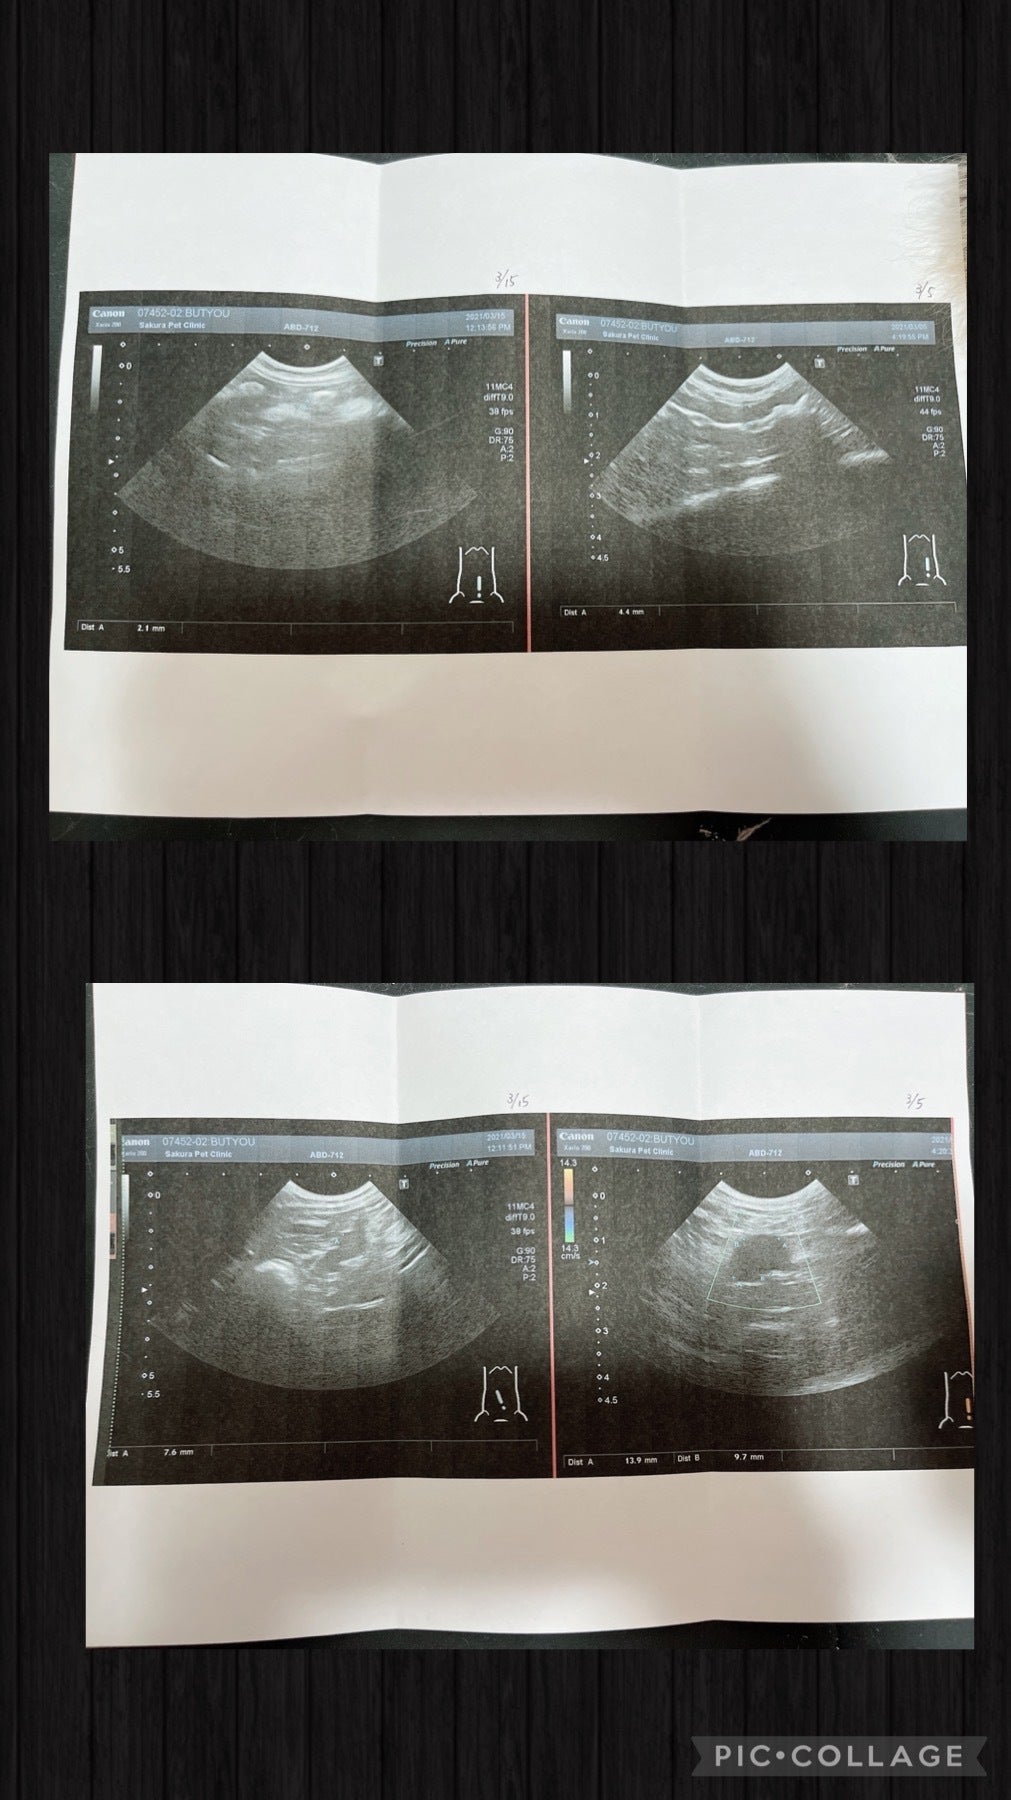

今出来る検査を全てしてもらうと

腸が二倍に腫れて肉芽腫がある

炎症がとても強過ぎる

先生からもFIPドライタイプ初期の疑いが高い

この日から部長はMUTIAN投薬スタートしました。

部長ちゃんは検査結果FIPドライタイプが確定し